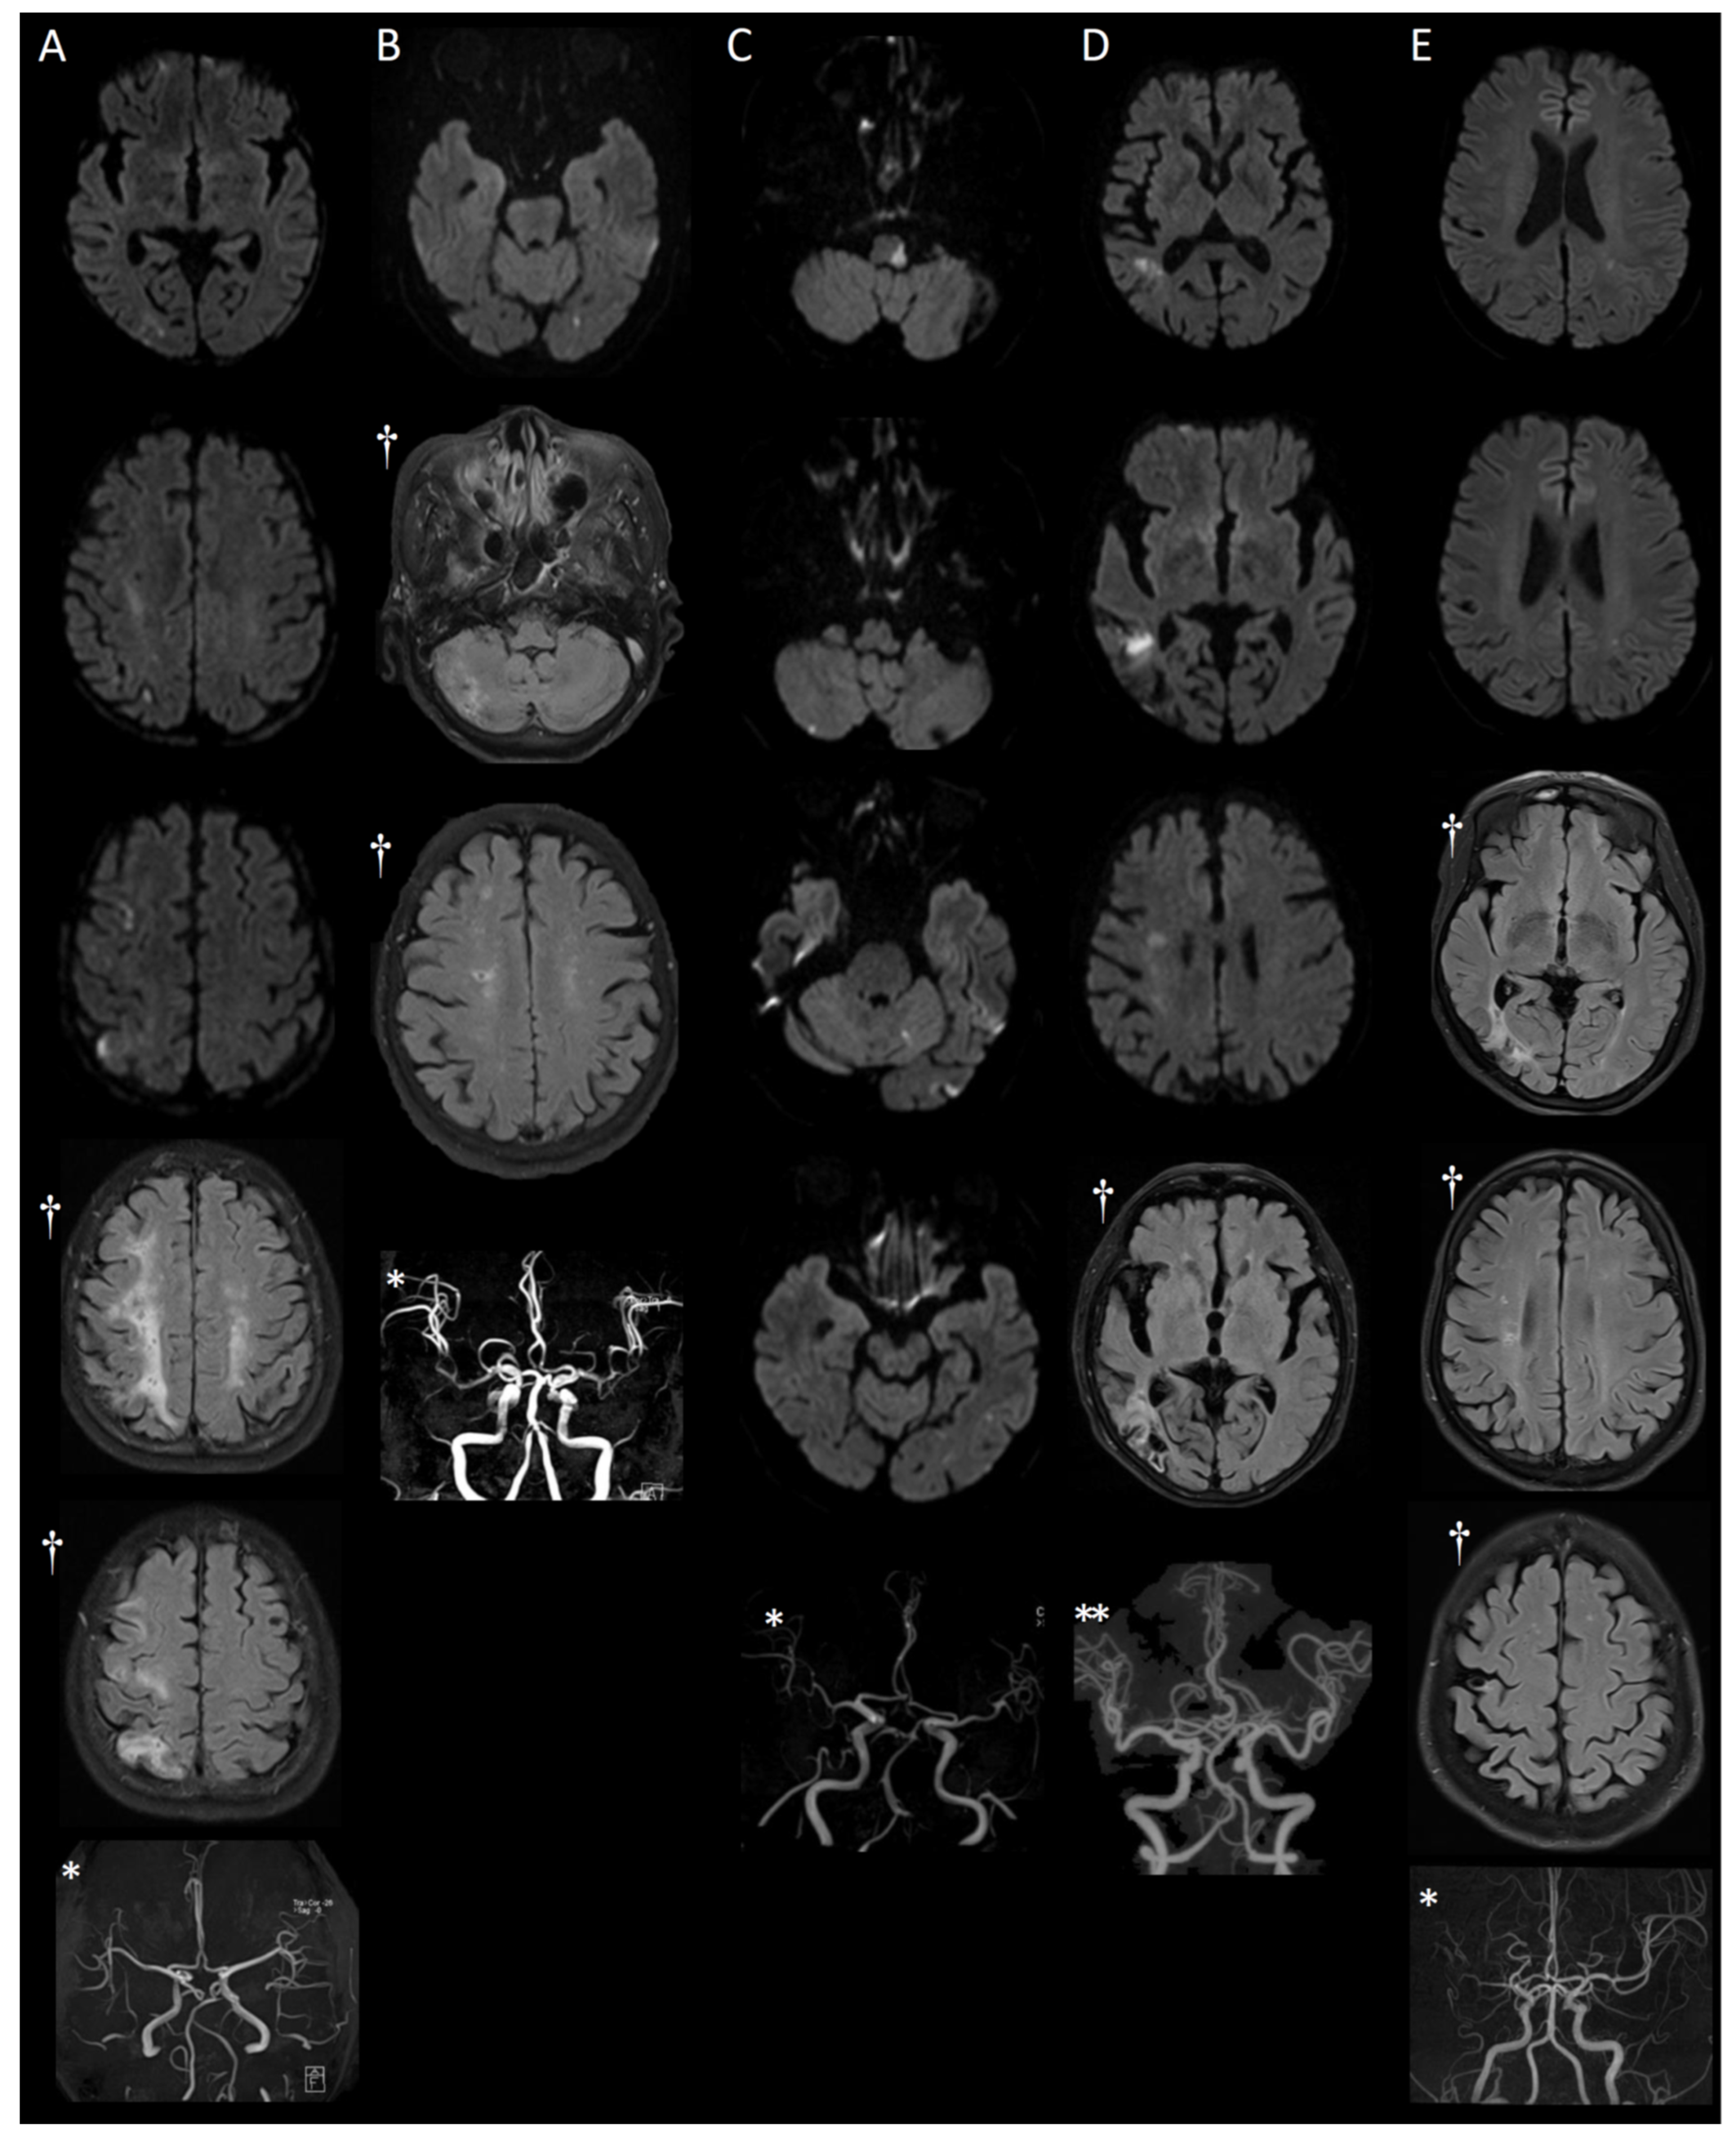

3.1. MRI Findings

3.2. Detailed Case Presentations